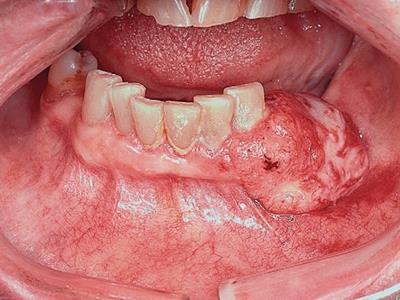

牙龈癌在口腔癌中仅次于舌癌而居第2位,组织学类型绝大多数为分化程度较高的鳞状细胞癌。牙龈癌好发于前磨牙区及磨牙区,下牙龈癌较上牙龈癌为多见,上下之比为2:1。牙龈癌发病年龄多为40-60岁,男性多于女性。

牙龈癌多源于牙间乳头及龈缘区,溃疡呈表浅、淡红,以后可出现增生。由于黏骨膜与牙槽突附着甚紧,较易早期侵犯牙槽突骨膜及骨质,进而出现牙松动,并可发生脱落。X线片可出现恶性肿瘤的破坏特征虫蚀状不规则吸收。

牙龈癌常发生继发感染,肿瘤伴以坏死组织,触之易出血。体积过大时可出现面部肿胀,浸润皮肤。